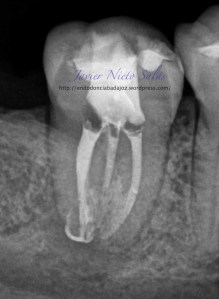

Empezaremos con el primer caso, un 4.7, se trata de una necrosis con afectación periapical.Ante las pruebas diagnósticas, nos fijamos en una fístula muy coronal, un sondaje vestibular puntual, esto nos hace pensar en un diagnóstico diferencial con un Sindrome de Diente fisurado. Sin aparente linea de fisura coronal, no vemos, con la ayuda de la magnificación, linea de fisura, lo que no nos descarta definitivamente que se trate de este síndrome de fisura, pues como ya sabemos pueden aparecer en diferentes tramos de la pieza, clasificando así los diferentes tipos.

Realizamos el tratatamiento de conductos con la sospecha del causante de la necrosis es una fractura vertical, pero no hemos podido ver la linea de fisura.

Se trataría de una cámara pulpar Tipo Ic según la clasificación por el método de Min:

El sistema de Obturación sería con condensación vertical.

(disto)                                                                     (mesio)